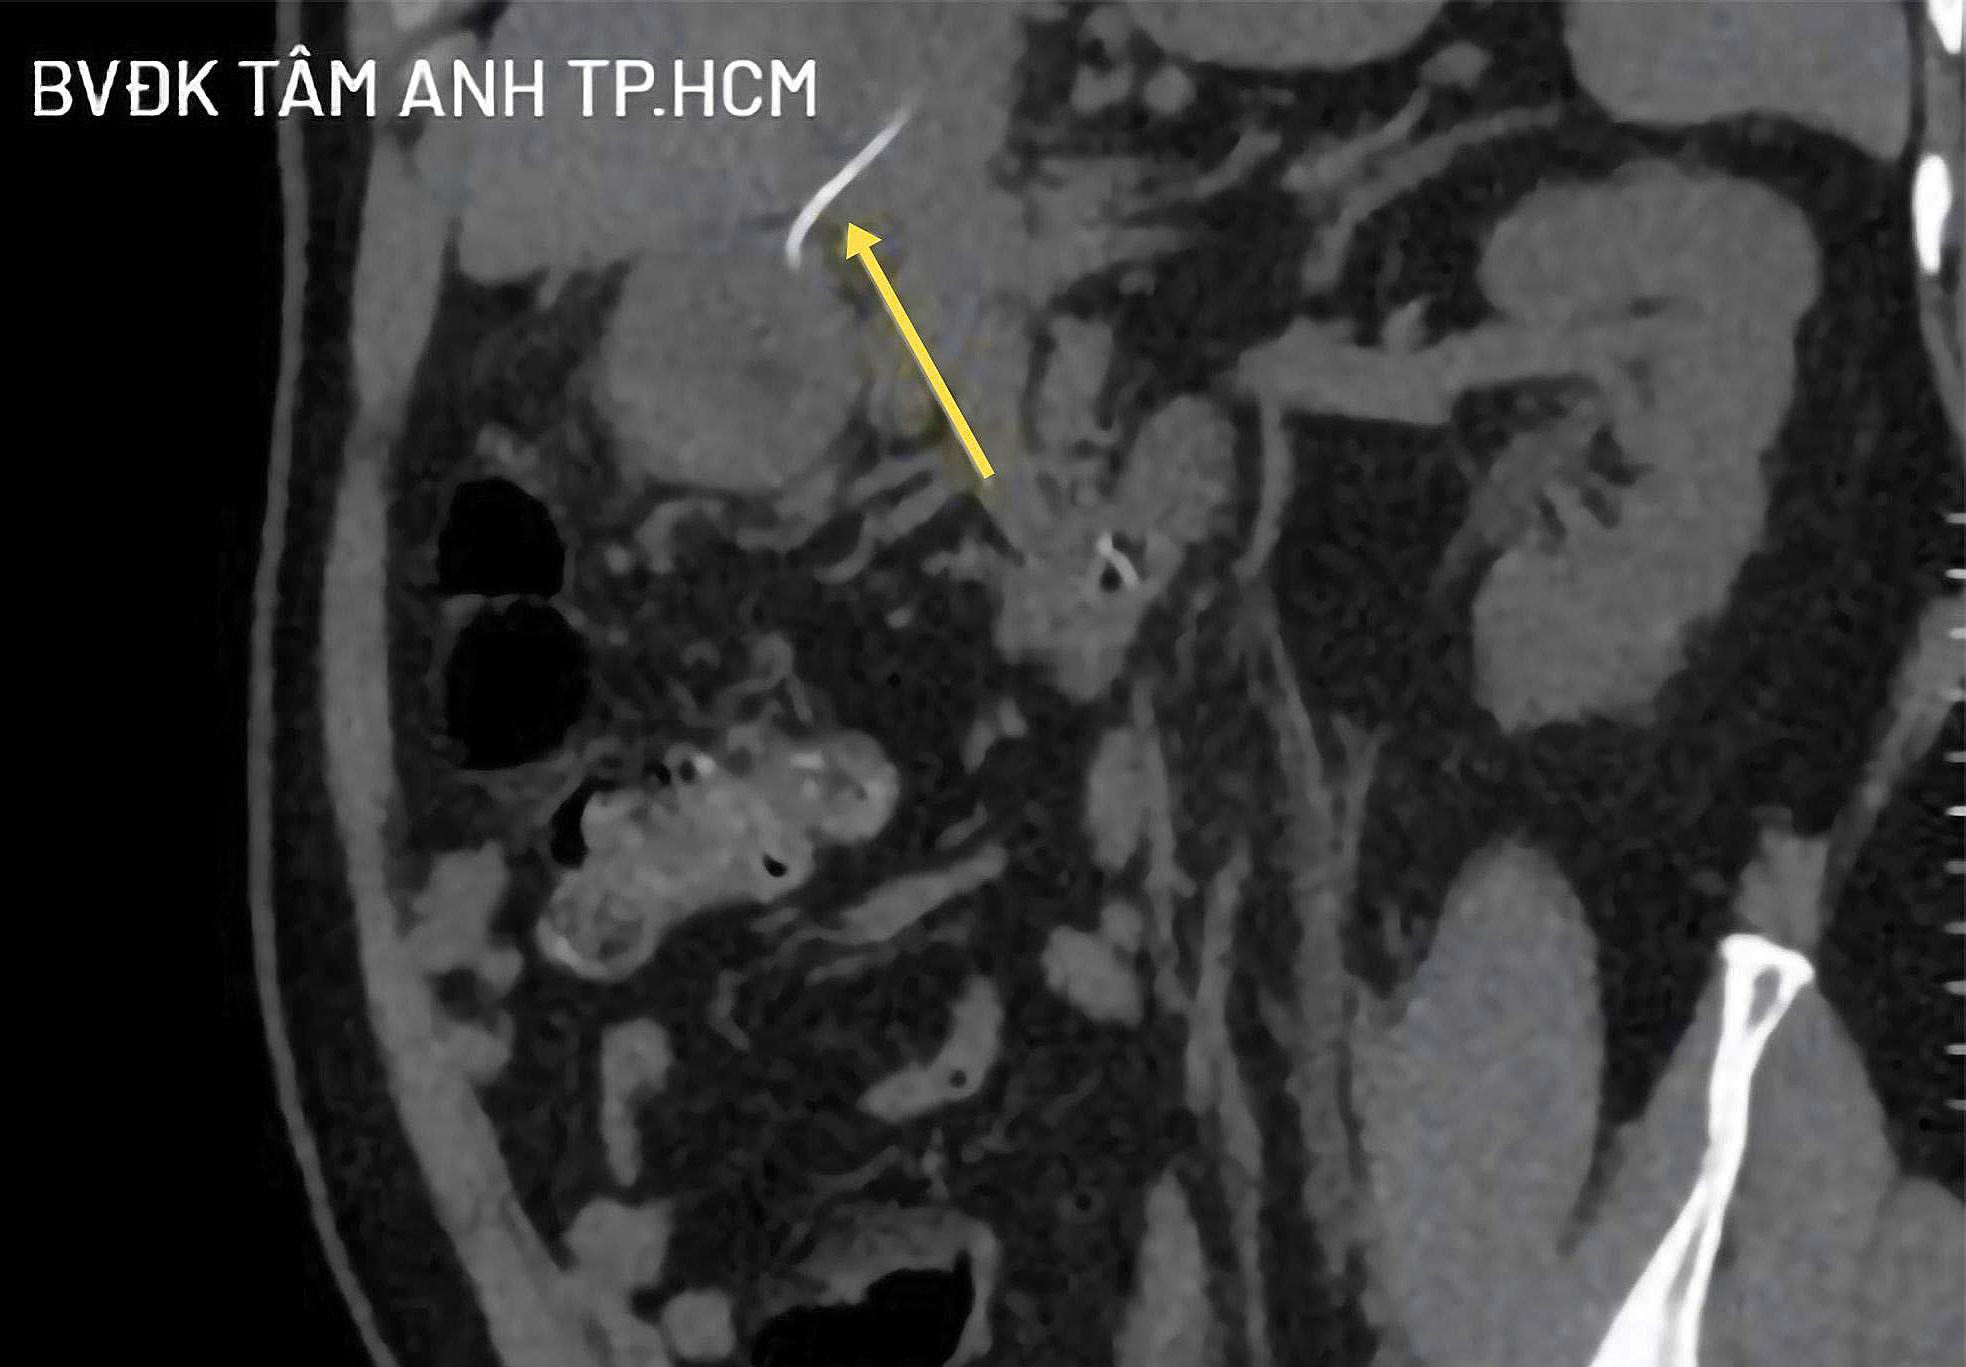

A CT scan confirmed a liver lesion measuring 4,5x3,8 cm, containing a foreign object nearly 4 cm long that had penetrated from the stomach wall into the liver parenchyma. Additionally, a smaller foreign object, 0,2 cm, was found in the sigmoid colon, though it had not yet perforated the colon wall.

CT images show the foreign object penetrating the stomach wall into the liver parenchyma (yellow arrow). Photo: Tam Anh General Hospital |